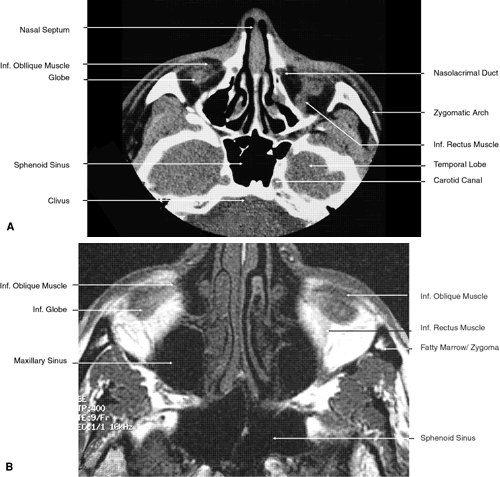

Fig. 22. Axial images at the level of inferior orbit. A. Computed tomography scan. B. T1-weighted magnetic resonance imaging.

Fig. 23. Axial images at the level of midorbit. A. Computed tomography scan. B. T1-weighted magnetic resonance imaging.